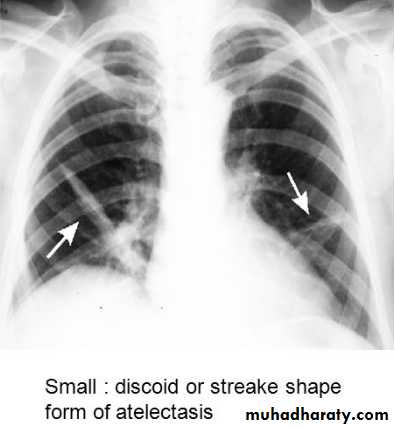

CT lung cavityPulmonary collapse(atelectasis): loss of volume of a lobe or lung, common causes: bronchial obst., pneumothorax or pl. effusion, linear(discoid) atelectasis.

Linear(discoid)atelectasis : is not secondary to bronchial obst., but due to hypoventilation, commonest cause is postop. Or post traumatic pain. The result is horizontally oriented band or disc of collapse